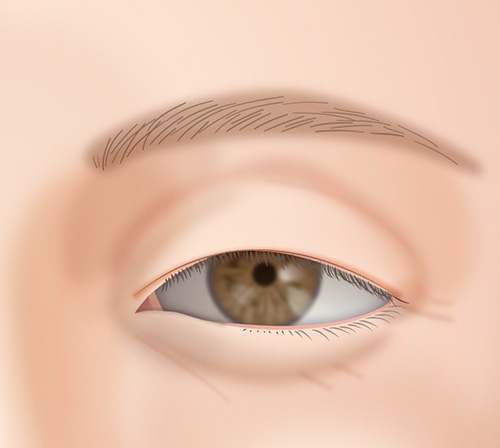

主に下まぶたのたるみ取りなどで皮膚を取りすぎると、常に粘膜が見えている状態になる場合があります。

改善を望むのであればとりすぎてしまった下まぶたを皮膚移植によって修正することが可能です。

ただし、機能の回復と引き換えに傷跡がかなり目立つ可能性があります。